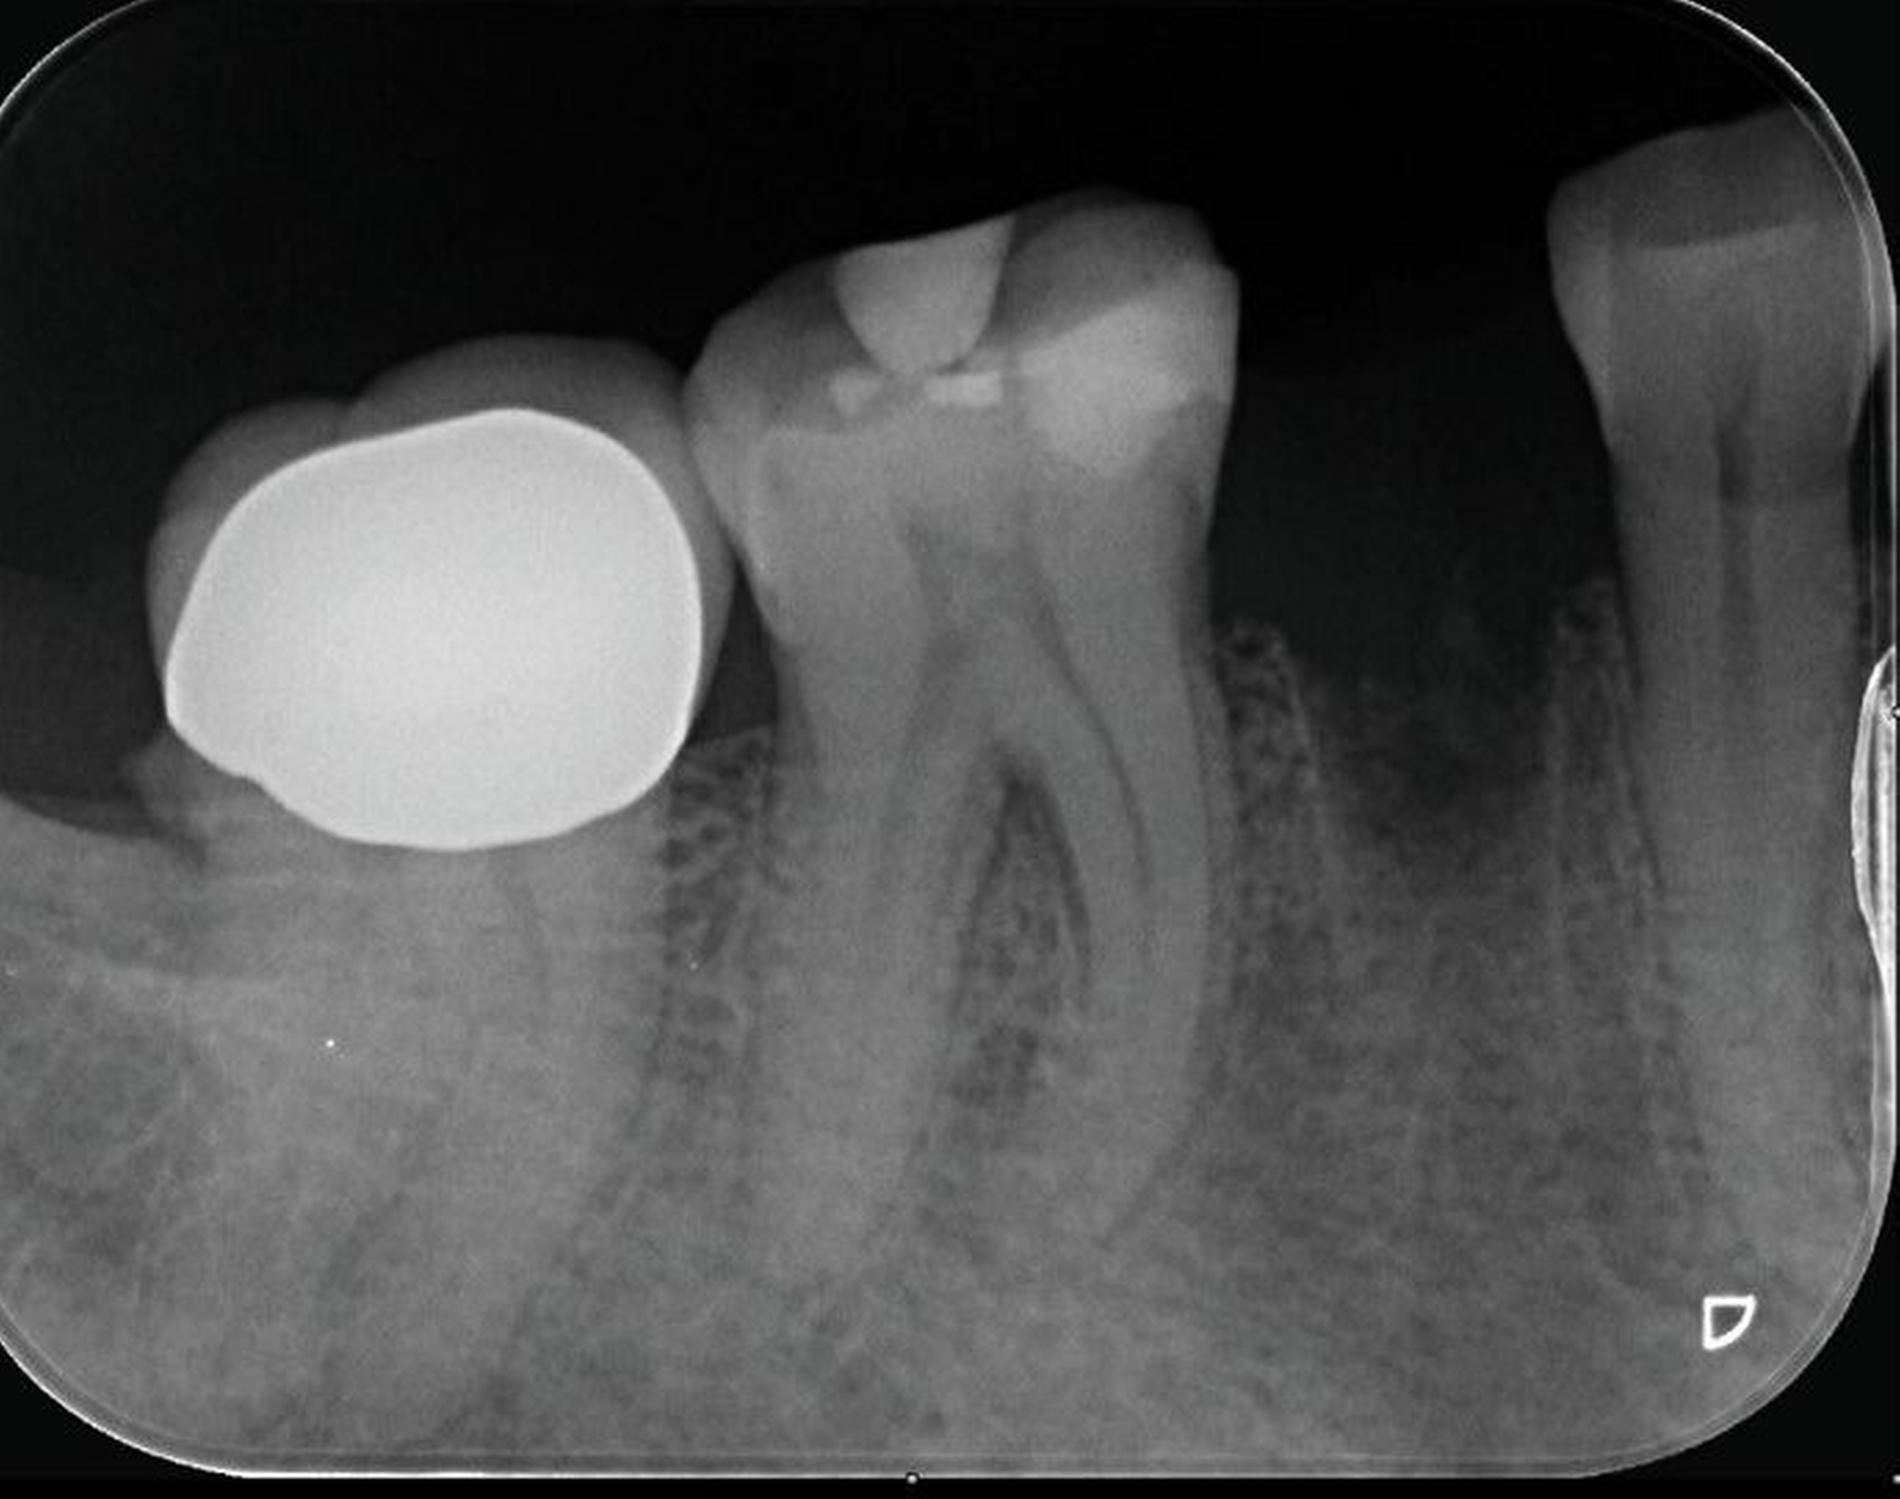

Nach antibiotischer Behandlung durch die orale Gabe von Clindamycin – aufgrund einer vermuteten Penicillinallergie – konnte vier Tage später der Zahn 45 extrahiert werden. Die Symptomatik persistierte jedoch und zeigte auch nach intraoraler Inzision und mehrfachem Streifenwechsel sowie Trepanation des Zahnes 46 keine Besserung (Abbildung 2). Die weitere Anamnese des Patienten war unauffällig.

Bei der Erstvorstellung in der Klinik für Mund-, Kiefer- und Gesichtschirurgie präsentierte sich das typische klinische Bild eines perimandibulären Abszesses. Noch am Aufnahmetag wurden daher die notfallmäßige Abszessinzision von extraoral sowie die Fokussanierung im Sinne der Extraktion des Zahnes 46 durchgeführt. Nach erneuter Bewertung der Penicillinallergie mittels PEN-FAST-Score wurde die Antibiose auf Amoxicillin/Clavulansäure umgestellt und bei regelrechtem stationärem Verlauf konnte der Patient in die ambulante Weiterbehandlung entlassen werden.